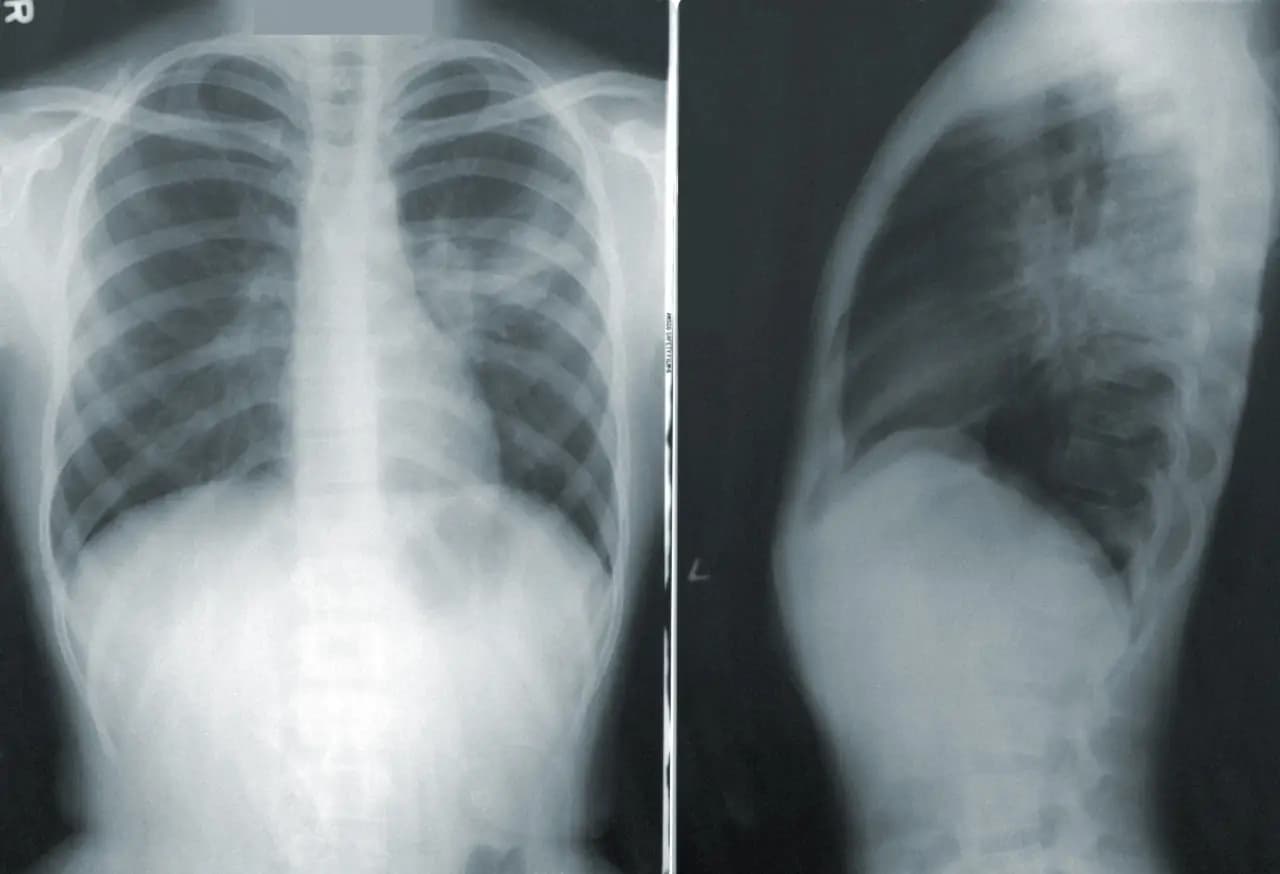

Forbes México . Bristol Myers se asocia con Microsoft para la detección del cáncer de pulmón impulsada por IA Bristol Myers Squibb anunció este martes la firma de un acuerdo con Microsoft para utilizar la plataforma de radiología basada en IA de la compañía tecnológica con el fin de acelerar la detección temprana del cáncer de pulmón. La colaboración implementará algoritmos de IA para radiología aprobados por la Administración de Alimentos y Medicamentos de EU (FDA) a través de la Red de Imágenes de Precisión de Microsoft, que analiza imágenes de rayos X y tomografías computarizadas para identificar enfermedades pulmonares y es utilizada por hospitales en Estados Unidos, informaron las compañías. Bristol Myers afirmó que las herramientas podrían ayudar a los médicos a detectar nódulos pulmonares difíciles de observar e identificar a algunos pacientes en etapas más tempranas de la enfermedad. La farmacéutica indicó que un objetivo clave de la colaboración es ampliar el acceso a la detección temprana en comunidades con acceso limitado a servicios médicos, incluyendo hospitales rurales y clínicas comunitarias en todo Estados Unidos. Te interesa: Regulador de EU aprueba fármaco de Bayer para combatir el cáncer de pulmón “Al combinar las soluciones de radiología altamente escalables de Microsoft con la profunda experiencia de Bristol en oncología y administración de fármacos, hemos imaginado un flujo de trabajo único basado en IA que ayuda a los médicos a identificar con rapidez y precisión a los pacientes con cáncer de pulmón de células no pequeñas y guiarlos hacia las vías de atención óptimas y terapias de precisión”, afirmó Alexandra Goncalves, vicepresidenta y directora de Salud Digital de Bristol Myers Squibb. Las compañías farmacéuticas recurrieron cada vez más a la inteligencia artificial para acelerar la I+D, apostando a que las nuevas herramientas de modelado y los laboratorios automatizados pueden mejorar la eficiencia de sus procesos de desarrollo. La semana pasada, AstraZeneca anunció que acordó la compra de Modella AI, con sede en Boston, para acelerar la investigación de fármacos oncológicos. Con información de Reuters Suscríbete a nuestro canal de YouTube y no te pierdas de nuestro contenido Bristol Myers se asocia con Microsoft para la detección del cáncer de pulmón impulsada por IA Forbes México Staff